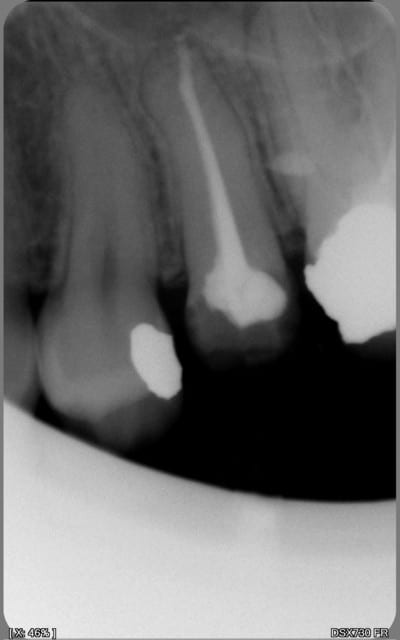

encore des radios,peut-etre assez moyen comme traitement...mais je vu pire...

les dernieres radios. patient en urgence ,abces... il voulait pas extraire la dent. j'ai lui bien explque et il a choisi de essayer de garder la dent. retrait,pas d'isolation avec la digue donc pas de tenon fibree,amalgam et screw post.traitement fait il ya 2 ans je crois.patient fidel de cabinet maintenent.